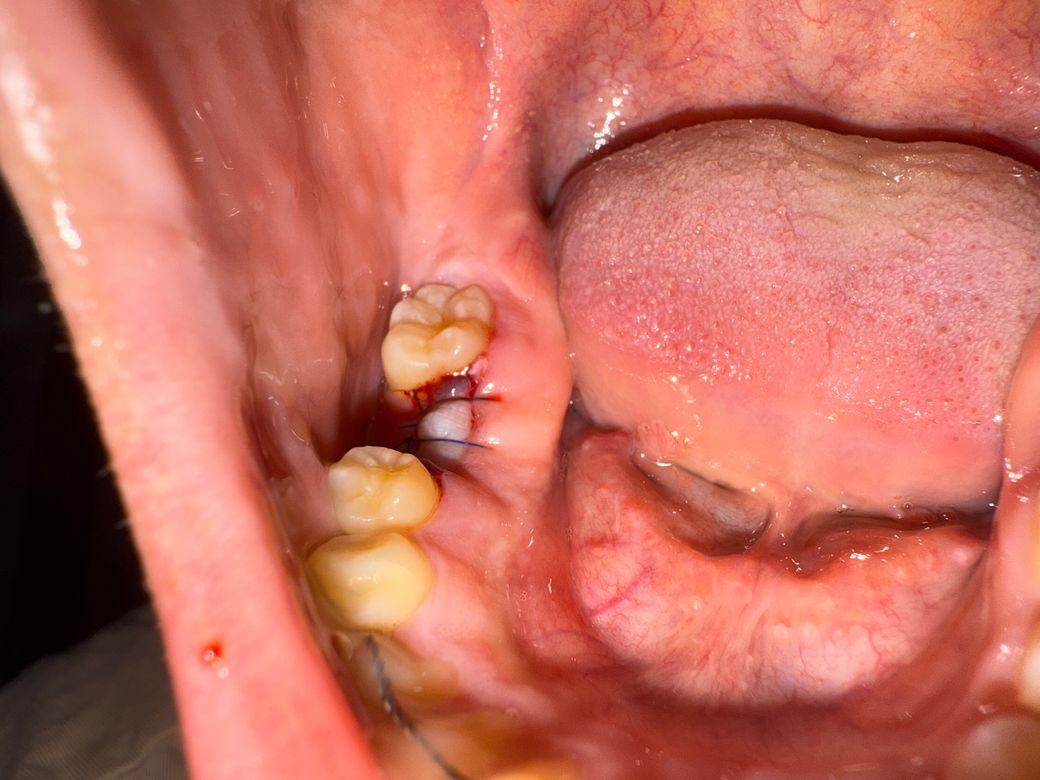

임플란트 1차수술 후 잇몸이 하얗게 변했어요

현재시각 06시 30분 일어나서 확인해보니 출혈이나 혈병은 사라졌으며 사진과같이 수술부가 하얗게 변한 상태입니다

• 1번 째 사진

• 2번 째 사진

임플란트 식립 후 염증 양상은 흔하게 있을 수 있으나 사진상으로 봤을때 단순 염증일지는 판단이 쉽지 않습니다 일단 항생제 복용하시고 며칠 추이를 지켜보시기 바랍니다

수술을 하고나서 잇몸이 치유되면서 하얗게 되는건 자연스러운 현상이니 너무 걱정하지 않으셔도 될것같습니다.

임플란트 수술을 하게 되면 해당 부위를 봉합을 해놓게 됩니다. 봉합을 해둔 부위에 압력이 상대적으로 많이 가해지게 되면 해당 잇몸에 혈액이 잘 모이지 않게 되어 흰색으로 보일 수 있습니다. 잇몸조직은 치유가 잘 되기 때문에 해당 부위를 자극하지 않는다면 시간이 지나면서 자연적으로 아물게 됩니다.